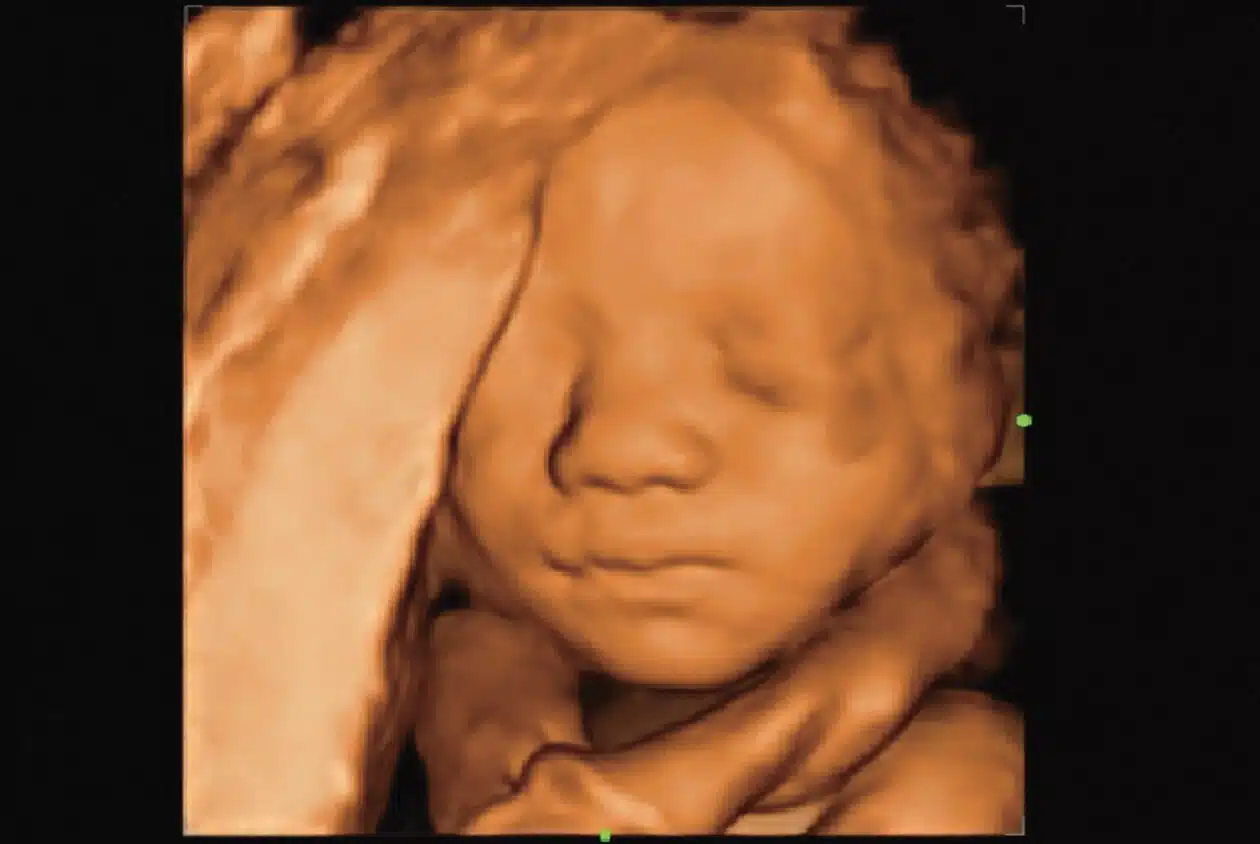

• Fetal-Face-3D_Imagyn-I9-1.jpg

3D Fetal Face

Smart Face

Fetal Face Optimization

Provides one-touch intelligent optimization of a fetal face and enhances workflow by automatically removing obstructions anterior to the fetal face, decreasing operator dependence and exam time.